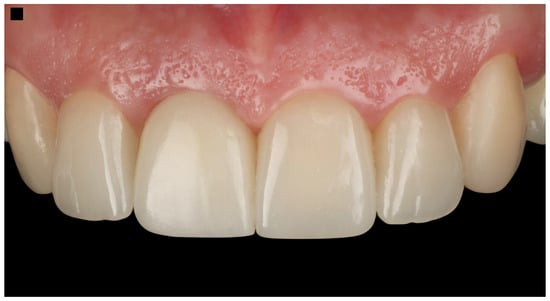

The patient expressed complete satisfaction with the final restorations, praising the natural shade and shape of the teeth. To protect the restorations from potential damage, the patient was provided with a custom-made night guard. Detailed oral hygiene instructions were given, emphasizing the importance of maintaining the health of the restorations and surrounding tissues. The patient was scheduled for regular follow-up visits every six months for professional dental prophylaxis and to monitor the condition of the restorations and periodontal tissues (Figure 10). At the three-year follow-up visit, the patient was still satisfied with the outcome.

Figure 10.

Final restorations.

3.2. Results of the Case Report

The workflow performed in this case illustration successfully addressed the patient’s esthetic and functional needs. The initial three-dimensional planning, including a detailed CBCT analysis, allowed for precise treatment preparation. This was followed by atraumatic tooth extraction and immediate implant placement using a surgical guide. The placement of a screw-retained provisional restoration and the subsequent final restoration were meticulously executed, resulting in a predictable and satisfactory outcome. The restorations on the adjacent teeth significantly enhanced the patient’s smile, improving overall symmetry, color, and shape. Additionally, the patient was provided with a custom-made occlusal guard to protect the restorations during nighttime grinding or clenching.